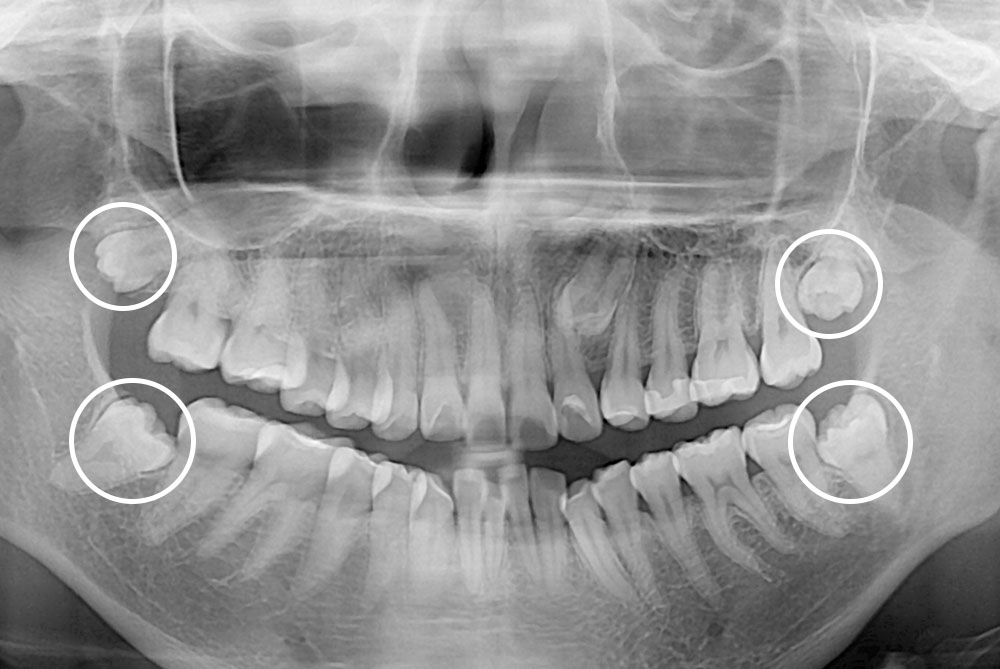

[사랑니] 매복 사랑니 발치

치료전 : 2019-04-26